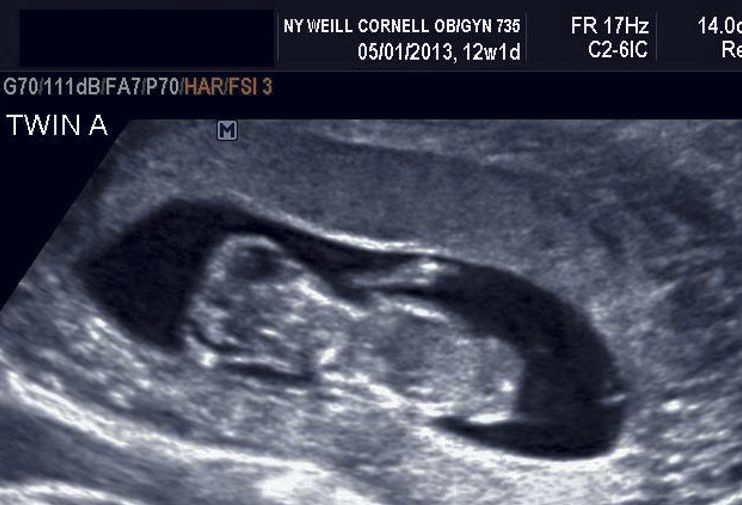

Late in the first trimester, the brain can be imaged in the transverse plane, identifying both hemispheres and midline structures. Anencephaly (absent skull and brain) is a major anomaly that can be identified.

First trimester holoprosencephaly

First trimester cephalocele

A profile view can identify a small mandible, or in this case a micrognathia, during the first trimester.

One of the most common abnormalities identified during the first trimester is the ventral wall defect, omphalocele.

First trimester gastroschisis

An enlarged urinary bladder (megacystis) in the first trimester can represent early evidence of bladder outlet obstruction.

First trimester polydactyly

Holoprosencephaly should not be missed in the first trimester and definitely not in the second semester.

Second trimester cephalocele

Second trimester anencephaly

Enlarged ventricles (ventriculomegaly hydrocephalus) in the second trimester can indicate several conditions.

Ventriculomegaly is present in the Dandy-Walker malformation, a malformation characterized by the absence of the middle portion of the cerebellum. It should not be missed during the second trimester.

Arnold-Chiari Type II malformation includes herniation of the hindbrain into the spinal canal, which causes the cerebellum to elongate and become distorted into a "banana" shape. It should not be missed during the second trimester.

Arnold-Chiari Type II malformation can also cause the frontal bones of the calvarium to collapse, causing a "lemon" shaped skull.

Another diagnosis that can be suspected based on second-trimester ultrasound is agenesis of the corpus callosum, a condition in which the large midline bundle of white matter connecting neurons in the two hemispheres is absent.

A profile view in the first and second trimester can identify a small mandible, or micrognathia.

Second trimester cleft lip and palate

Median or bilateral cleft lip can be suspected based on profile views.